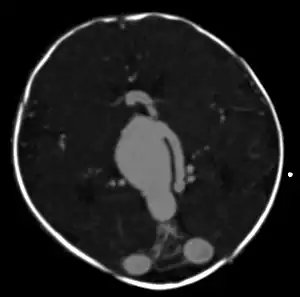

| Large arteriovenous malformation of the parietal lobe | |

vein of Galen malformation

A cerebral AVM diagnosis is established by neuroimaging studies after a complete neurological and physical examination.[5][12] Three main techniques are used to visualize the brain and search for an AVM: computed tomography (CT), magnetic resonance imaging (MRI), and cerebral angiography.[12] A CT scan of the head is usually performed first when the subject is symptomatic. It can suggest the approximate site of the bleed.[3] MRI is more sensitive than CT in the diagnosis, and provides better information about the exact location of the malformation.[12] More detailed pictures of the tangle of blood vessels that compose an AVM can be obtained by using radioactive agents injected into the blood stream. If a CT is used in conjunctiangiogram, this is called a computerized tomography angiogram; while, if MRI is used it is called magnetic resonance angiogram.[3][12] The best images of a cerebral AVM are obtained through cerebral angiography. This procedure involves using a catheter, threaded through an artery up to the head, to deliver a contrast agent into the AVM. As the contrast agent flows through the AVM structure, a sequence of X-ray images are obtained.[12]